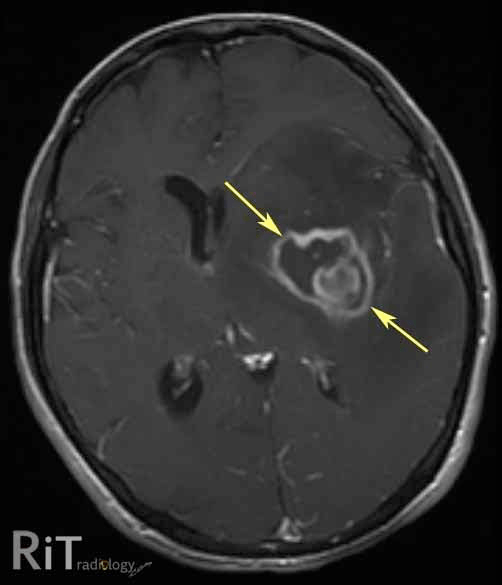

What two CNS mass lesions are associated with HIV/AIDS

1) Toxoplasmosis (multiple ring-enhancing lesions w/ edema)

2) CNS lymphoma (hyperdense, round enhancing lesions)